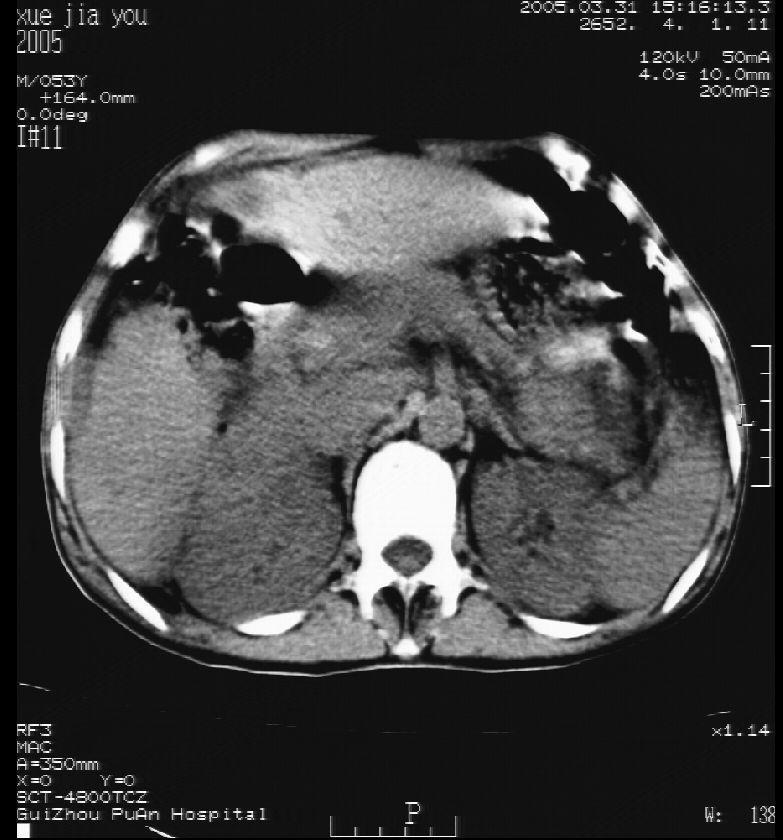

男 55岁  反复上腹痛1年,伴恶心呕吐。2005年做第一次检查后,到外院做b超检查提示肝囊肿,未做任何手术。2006年做过胆总管结石术。骨窗未见异常

这个病灶很有意思,怎么可能没有了呢?我考虑当时很可能是肝脏脓肿(b超示囊肿是有可能误诊的,因为影像表现都是低回声吗?),现在脓肿吸收了,肝脏萎缩,肝裂增宽了.别的肝叶代偿增大,不过现在左内叶的确有个占位,肝内多发结石,脾脏比以前大,不排除有肝硬化可能.建议增强扫描给于定性!!!!

肝硬化\\脾大,肝左叶肝癌可能性大,建议增强扫描.肝内胆管多发性结石.

1, 肝硬化,脾大;2,肝左叶肝癌可能性大,建议增强扫描.3,肝内胆管多发性结石.

考虑肝内胆管多发结石引起的肝内局部炎症,这样可以解释2005年肝右叶病灶的吸收和左叶新病灶.

肝硬化、脾大、肝内胆管多发结石。肝左叶低密度占位。建议增强扫描.排除肝癌